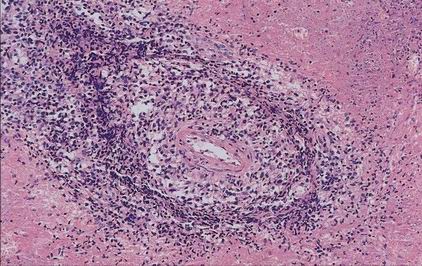

Lymfoproliferace

Diferenciální diagnostika malobuněčných tumorů

V klasické histologii podobné až nerozpoznatelné

K diferenciální diagnóze nezbytné imunohistochemické (IHC) vyšetření větším počtem protilátek

Bez IHC je přesná diagnóza nejistá